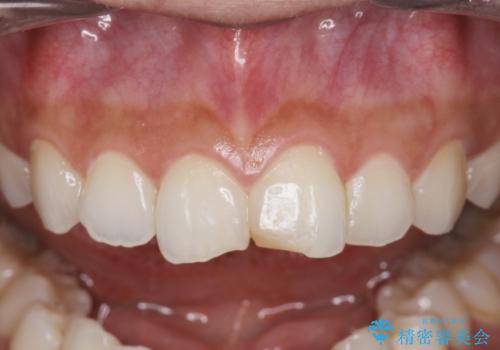

すり減った前歯の形態回復

- すり減ってしまった前歯の審美性の回復を希望され来院されました。

何度かレジン修復を試みたものの、脱離しやすく変色も気になる、とのことでセラミッククラウンによる審美性の回復を計画します。

自然な色調のセラミッククラウンで審美性を回復することができ、大変満足いただけました。